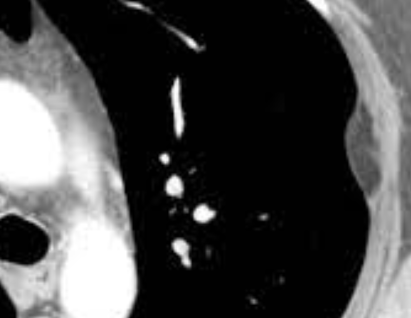

• Tumeur la plus fréquente de la plèvre

• N’érode pas les Cotes

plevre plèvre pleurale lipoma graisseuse graiseus